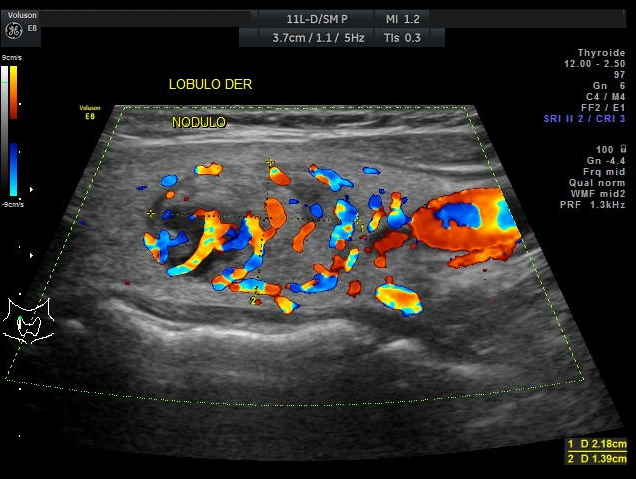

Una vez revisados los nuevos paraclínicos, la paciente es mantenida con la misma dosificación de Levotiroxina de 50mcg vía oral al día en ayunas. A los tres meses de tratamiento se observa una mejor condición de la paciente la sintomatología depresiva ha mejorado continua tomando la Levotiroxina a dosis de 50mcg diarios y la Fluoxetina 50 mg diarios, una dieta adecuada y terapia física. Se realizan nuevos controles de sangre con resultados normales (Tabla 4) y una nueva ecografía tiroidea en la cual se observa mejor las características ecográficas del nódulo tiroideo previamente observado, describiéndose semisólido, encapsulado de 3,7cm, clasificación de riesgo TIRADS 4 (Figuras 5–6). Se le explica a la paciente el riesgo que ofrece un nódulo de éste tipo, pero ella rehúsa realizarse la Punción por Aguja Fina guiada por ultrasonido para la valoración citológica del nódulo tiroideo.

Tenemos una paciente cuya sintomatología es compatible a una enfermedad tiroidea como un hipotiroidismo, además se acompañan otros síntomas como el vértigo, edema en miembros inferiores, sobrepeso, signos depresivos. Al mirar esta analítica sanguínea se observa claramente la presencia de una PCR incrementada, niveles de Colesterol total y LDL elevados, hiperbilirrubinemia, hiponatremia, TSH incrementado con T4 un poco por debajo de su rango normal. La ecografía tiroidea determina un nódulo único derecho de consistencia sólida con microcalcificaciones clasificado dentro de un TIRADS 4. Posteriormente se le realiza valoración sérica de Anti–TPO, ANA-HEP con resultado positivo lo que podría orientar a una enfermedad tiroidea autoinmune en este caso una Tiroiditis de Hashimoto.

Así mismo los nódulos pueden ser capsulados la mayoría de estos son benignos, y no capsulados que son irregulares no se aprecia el signo del halo en la investigación ecografía y suelen ser malignos. Pueden existir uno o varios nódulos tiroideos que según a la clasificación TIRADS se categoriza el riesgo de malignidad y cuando realizar la citología, en TIRADS 3 es recomendable un seguimiento ecográfico, en TIRADS 4 y 5 se sugiere la citología para diagnóstico, el examen de punción por aguja fina es sencillo mediante normas de asepsia, a veces no es necesario usar anestésico local, con el cuello en extensión y la paciente cómoda se ha de puncionar mediante guía ecográfica directamente al nódulo palpable22,24. De igual manera los marcadores tumorales en caso de sospechar malignidad son los niveles séricos de tiroglobulina y calcitonina. El control se debe realizar periódicamente ya sea ecográfico como con los marcadores tumorales, pero si la paciente nota crecimiento del nódulo se ha de realizar la PAAF diagnostica y posible tiroidectomía23,24.

En el presente caso se concluye que la paciente presenta Enfermedad Tiroidea Autoinmune como la “Tiroiditis de Hashimoto” por la clínica típica de un Hipotiroidismo correlacionado con los exámenes de sangre de hormonas tiroideas en la que se aprecia TSH incrementada ante una T4 ligeramente disminuida, además del resultado positivo de Anti–TPO. La historia familiar de parte materna de hipotiroidismo se la cataloga dentro de personas predispuestas de ETAI, el 90% de estos pacientes tienen anticuerpos antiperoxidasa y antitiroglobulina positivos. Como se demuestra se ha relacionado la presencia de susceptibilidad genética y una serie de factores ambientales desencadenantes como por ejemplo el tabaco, estrés, aporte de yodo radioactivo. La ETAI se produce por el daño directo a los folículos tiroideos riesgo de formación de nódulos; lo que en este caso la paciente ha presentado de forma casual un nódulo que por ser mayor a 10mm y una característica grado 4 de TIRADS en investigación ecográfica se le recomienda la citología por una posible malignidad. El aporte inadecuado de levotiroxina le ha llevado a sufrir síntomas típicos de hipotiroidismo, y exacerbación por un metabolismo alterado de manifestaciones clínicas de otras patologías.